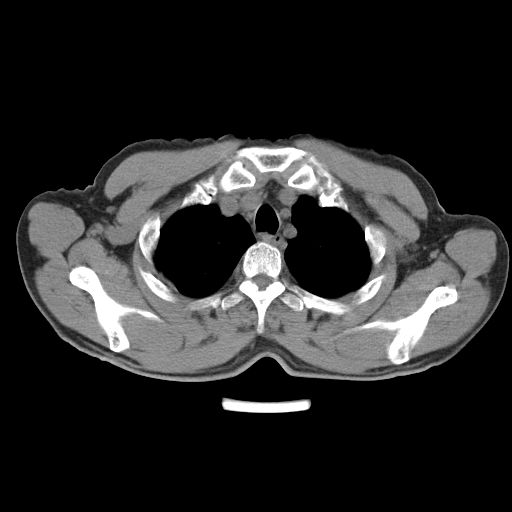

以下是引用心路寻觅在2010-3-1 10:23:00的发言:[br]1、考虑左肺上叶周围型肺癌[br]2、右上肺陈旧性病灶。[br][br][本贴已被 心路寻觅 于 2010-3-1 10:40:18 修改过]

以下是引用shuiyuan在2010-3-1 10:45:00的发言:[br]考虑左肺上叶中心型肺癌伴阻塞型炎症,邻近胸膜受侵。